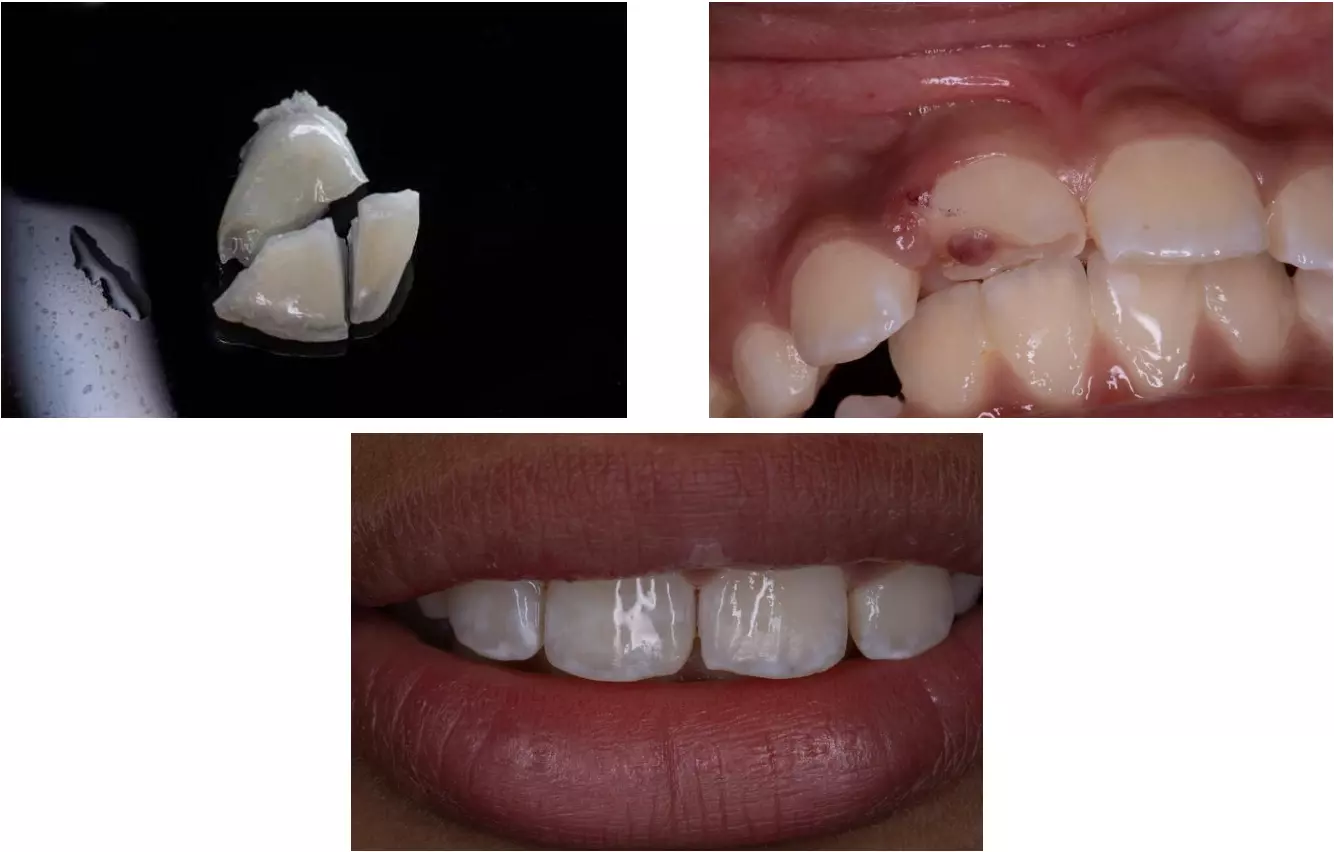

Пример восстановления зуба фрагментами после травмы

Пример реставрации фрагментом зуба

Пример реставрации фрагментом зуба. Отреставрирован нижний центральный резец слева. Рентген сразу и через 12 месяцев после лечения.